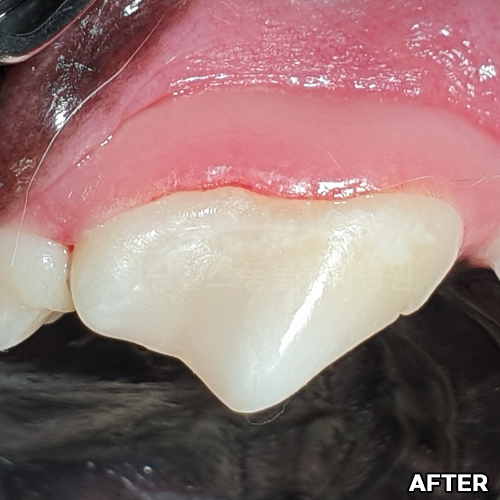

[대형견 마라노이즈 송곳니 레진치료 - 강아지치과 법랑질 저형성증 -]

[구멍난 강아지 치아 레진치료 전후]

[깨진 강아지 치아 레진치료 전후]

[강아지앞니 치료]

[강아지 치아의 구멍 레진치료 후 2주 경과]

[15년 노령견의 어금니 레진치료]